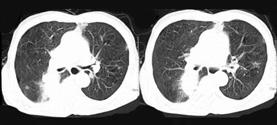

- 单项选择题72岁,男, 呼吸急促、气喘4个月,请结合胸片和CT, 选出最可能的诊断 ( )

A、肺癌

B、错构瘤

C、肺结核

D、韦格肉芽肿

E、支气管腺瘤